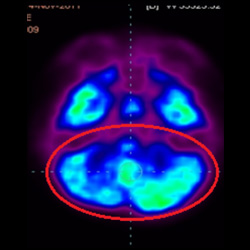

干細胞治療腦癱后改善的客觀放射學證據

細胞治療后,藍色和黑色區域減少,并且看到更活躍的區域。這表明損傷減少并改善了大腦功能。

這證明細胞療法是治療腦癱兒童安全有效的方法。細胞療法可以更新大腦損傷的核心,并且可以通過 PET CT 掃描來監測大腦的改善情況。這些細胞療法與標準治療一起促進腦癱兒童的生長和改善。